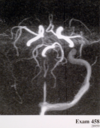

MRA of COW - Axial

•1 - Anterior Cerebral

- 2 – Middle Cerebral

- 3 – Posterior Cerebral

- 4 – Basilar

- 5 – Vertebral

- 6 – Internal Carotid

MRA of COW - Coronal

•1 - Anterior Cerebral

- 2 – Middle Cerebral

- 3 – Posterior Cerebral

- 4 – Basilar

- 5 – Vertebral

- 6 – Internal Carotid

- L ICA aneurysm

- No flow in basilar artery

- R MCA dissection

- Basilar artery dissection

No flow in basilar artery

- High grade prox L MCA stenosis

- R carotid body tumor

- No flow in basilar artery

- Dolichoectatic basilar artery

High grade proximal MCA stenosis (loss of flow signal in proximal L MCA)